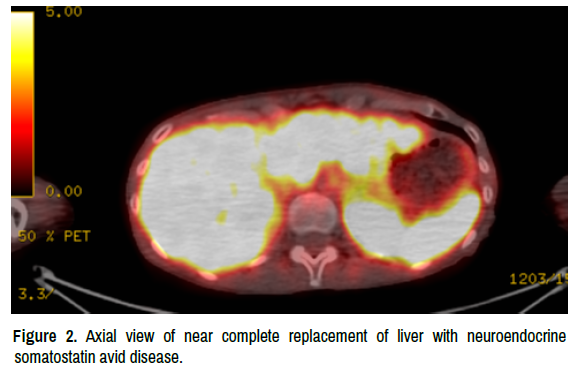

In November 2021, a repeat liver biopsy was performed for consideration of a clinical trial. The pathologic diagnosis based on histomorphology and immunophenotype suggested metastasis from known breast primary carcinoma positive for ER, PR, synaptophysin, chromogranin-A, and GATA- 3. The patient had undergone all standard chemotherapy treatments with no positive outcomes. Disease progression was present throughout all treatment protocols, and hospice was then the recommended standard of care. In January 2022 upon further testing of the November 2021 specimen there showed a strong somatostatin receptor subtype 2 immunohistochemistry (SSTR2 IHC) over expression. This was followed up on April 2022 with a 64 Cu-DOTATATE PET/CT scan, specifically to determine whether a tumor is a somatostatin receptor-expressing and avid neuroendocrine tumor. The test suggested the presence of extensive metastasis, most prominently in the liver with high radiotracer uptake consistent with the findings of a neuroendocrine tumor. Uptake in the liver on this test (max standard uptake value 15) is much more intense than the fluorodeoxyglucose positron emission tomography (FDG PET) scan (max standard uptake 9). Additionally, extensive bone metastasis with intense uptake was observed, with mild adenopathy in the chest and upper abdomen [4] (Figures 1-4).

integrative-oncology-neuroendocrine

Figure 2. Axial view of near complete replacement of liver with neuroendocrine somatostatin avid disease.